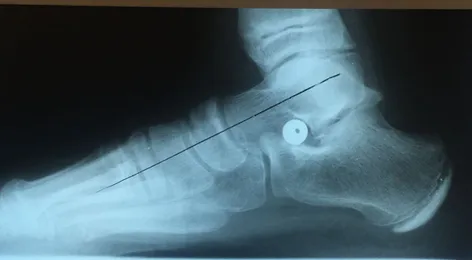

Pre and Postop X-rays Subtalar Joint Implant (Below)

Patient JD

Pre and Postop Subtalar Implant and Percutaneous Achilles Lengthening Below. The first pics show wedging of the distal tibia physis causing ankle valgus due to constant pressure caused by the severity of the flatfoot (JT)